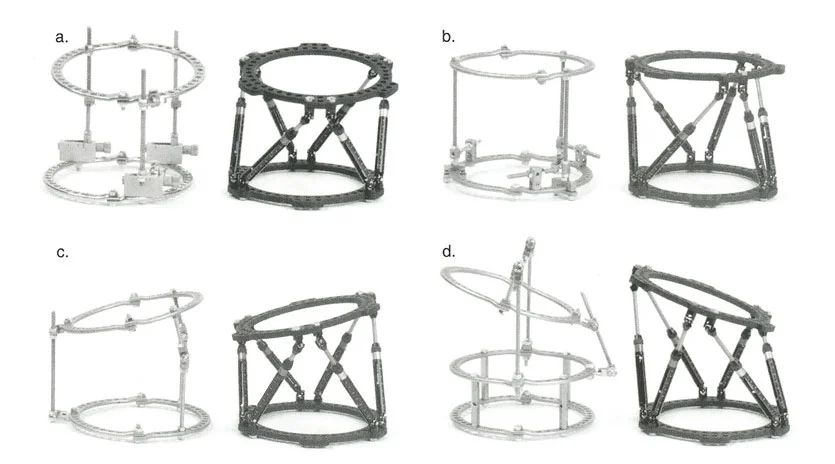

المثبتات الخارجية: أنواعها ودورها

تُستخدم أنواع مختلفة من المثبتات الخارجية لتطبيق مبادئ بالي وإليزاروف:

- مثبتات إليزاروف الدائرية الكلاسيكية: تتكون من حلقات معدنية متصلة بالعظم بأسلاك رفيعة، وتسمح بتصحيح متعدد المستويات.

- أنظمة الهيكسابود الحديثة (مثل جهاز تايلور الفراغي Taylor Spatial Frame): تستخدم ست دعامات متداخلة (struts) متصلة بحلقتين. يتم التحكم فيها بواسطة برنامج حاسوبي يقوم بحساب التعديلات اليومية بدقة فائقة لتصحيح التشوه في ستة اتجاهات.

- المثبتات أحادية الجانب (Monolateral Fixators): تتميز بقضيب واحد يمتد على طول الطرف، وتستخدم غالبًا للتصحيحات الخطية أو الزاوية البسيطة.